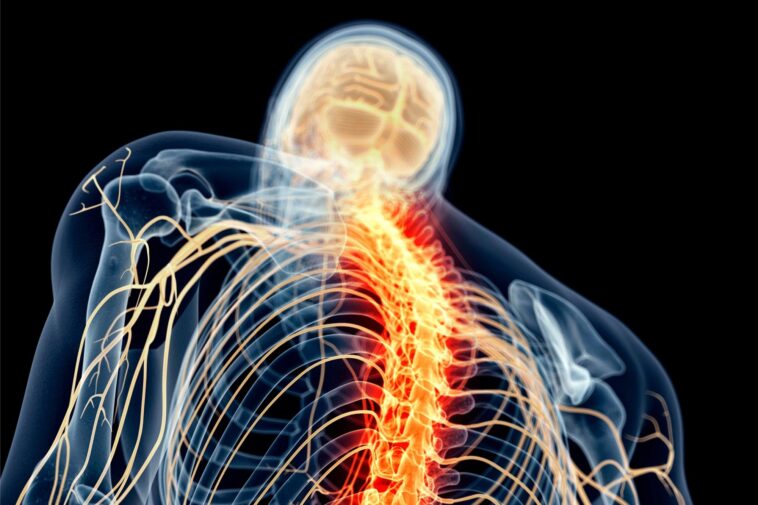

Des recherches récentes révèlent que la gabapentine peut prévenir le dysfonctionnement métabolique provoqué par des lésions de la moelle épinière en inhibant les protéines neuronales hyperactives, offrant ainsi une stratégie de traitement précoce potentielle pour atténuer les maladies cardiométaboliques associées.

Une nouvelle étude animale suggère que des affections telles que le diabète, les crises cardiaques et les maladies vasculaires, couramment diagnostiquées chez les personnes souffrant de lésions médullaires, pourraient être liées à une activité neuronale inhabituelle suite à la lésion. Cette activité peut provoquer une fuite et une accumulation des composés des tissus adipeux abdominaux dans le foie et d’autres organes, selon une nouvelle étude animale.

La gabapentine inhibe une protéine neurale qui, une fois le système nerveux endommagé, devient hyperactive et provoque des problèmes de communication – dans ce cas, affectant les neurones sensoriels et le tissu adipeux abdominal auquel ils envoient des signaux.